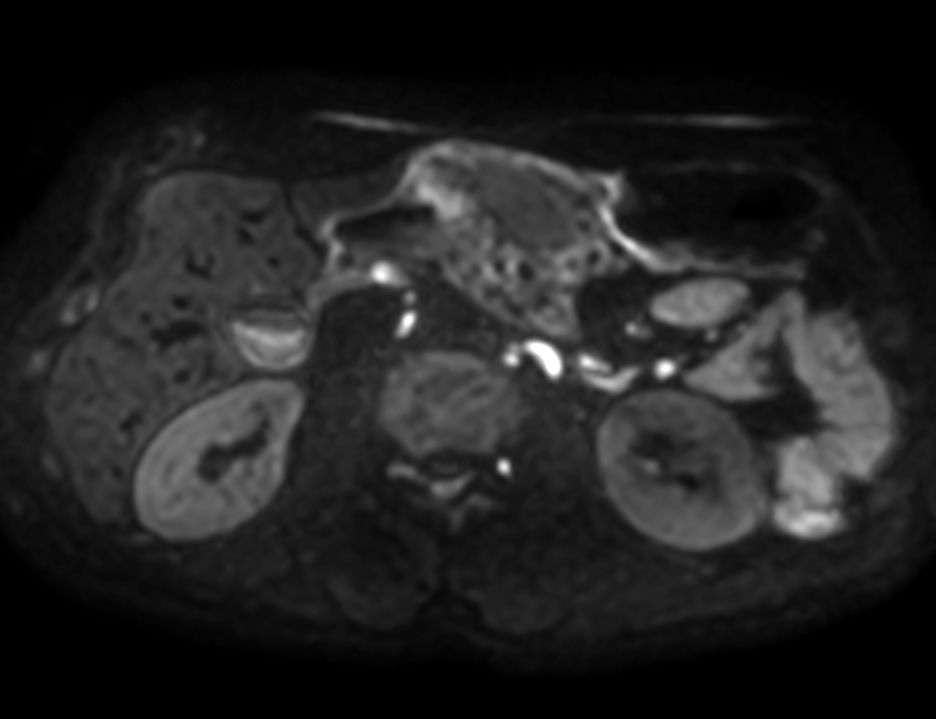

Axial DWI b10003mm slices

Axial DWI b503mm slices

Axial DWI b6003mm slices

Axial DWI ADC3mm slices

Axial DWI b504mm slices

Axial DWI b6004mm slices

Axial DWI ADC4mm slices

The benefits of enhanced Vega HP gradients in DWI is the reduced distortion and increased signal which can be traded for thinner slices.

Comparisons of DWI sequences with 4 mm versus 3 mm slice thickness are included.